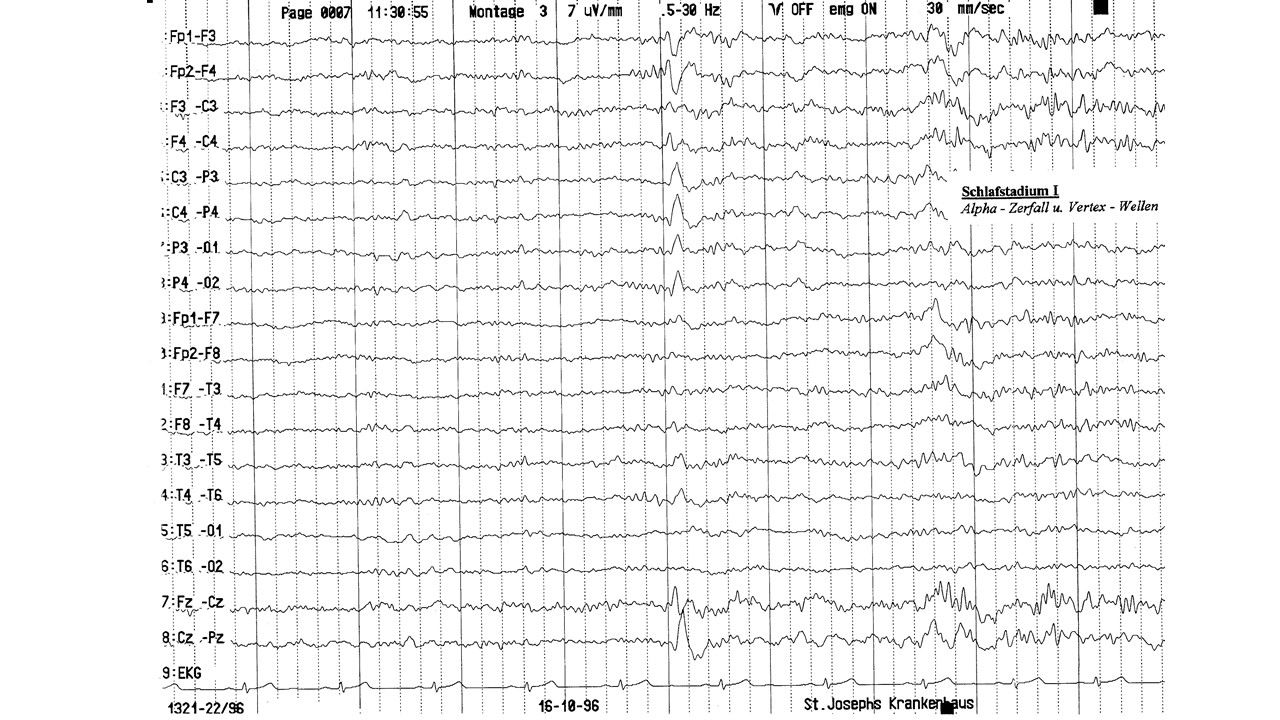

folie627.jpg